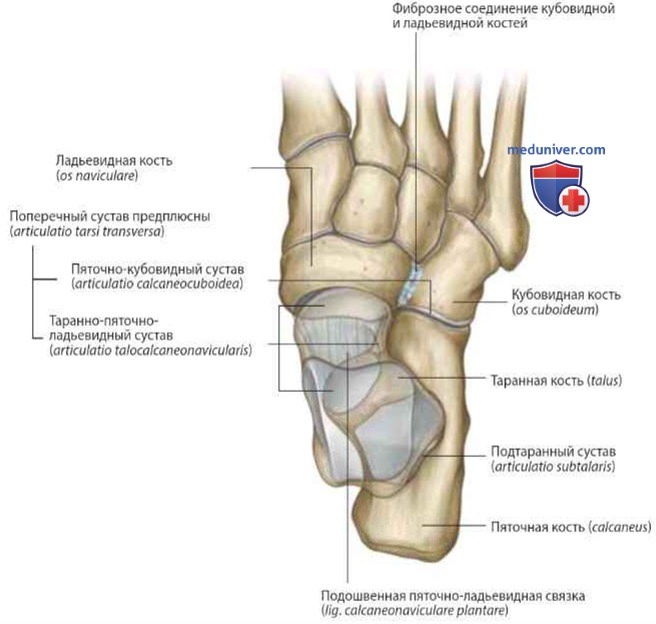

Анатомия суставов Шапарова и Лисфранка: фото и информация